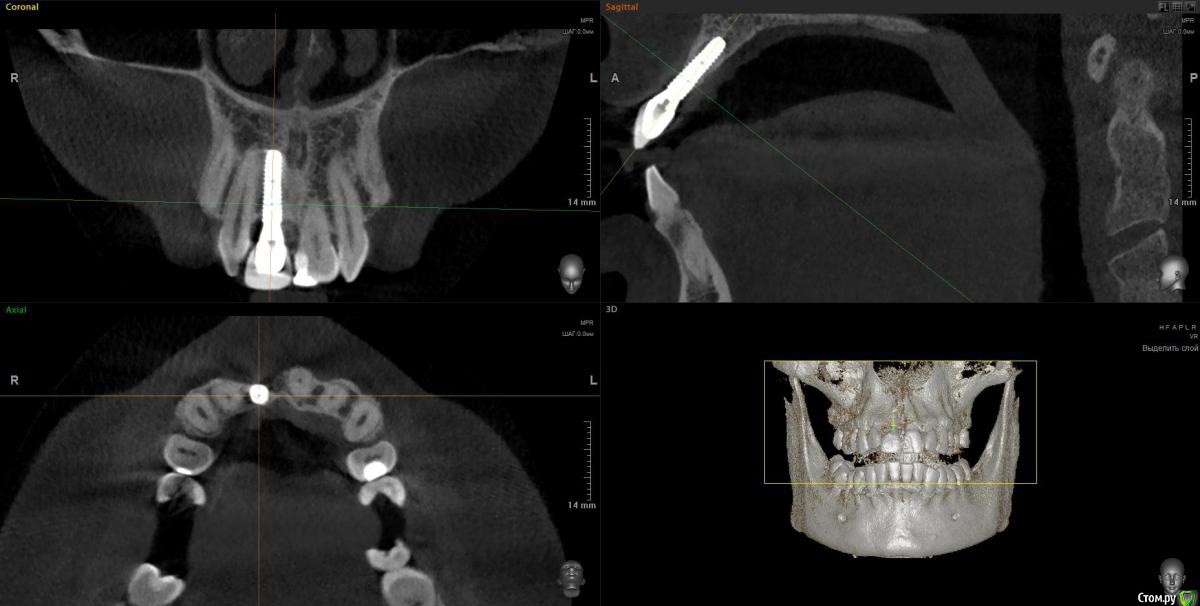

Doctor Vlad Опубликовано 6 сентября, 2020 Поделиться Опубликовано 6 сентября, 2020 Приветствую всех! Такая ситуация. Лет 5 назад имплантация. Кто делал уже не существует. Слизистая в области 11 тонкий биотип. Просвечивается имплант. высокая линия улыбки и выглядит просто темным пятном. Не красиво короче. В прошлом гноилось. Абатмент золотым колечком оголен чутка. кт приложен скрин. Витков 5 вестибулярно не в кости. коронка возможно перегружена прикусомМой план: начать с десны. если эстетически будет удовлетворительно и процесс остановится хорошо. коронку из прикуса вывести ещено остается вариант удаление импланта костная аугментация и десневая и все по новой Ссылка на комментарий

колесников Опубликовано 6 сентября, 2020 Поделиться Опубликовано 6 сентября, 2020 Можно попробовать,но очень вестибулярное положение платформы. Полировать нужно если графтинг планируется,а тут только гамборенинг вытянет-расщепится тоннельно. Абатмент надо сменить,максимально заузить. 2 Ссылка на комментарий

Дмитрий Л. Опубликовано 7 сентября, 2020 Поделиться Опубликовано 7 сентября, 2020 Тёмненькое над зенитом коронки это что? Платформа винта? Ссылка на комментарий

Doctor Vlad Опубликовано 7 сентября, 2020 Автор Поделиться Опубликовано 7 сентября, 2020 Тёмненькое над зенитом коронки это что? Платформа винта?там золотого цвета что-то. скорей всего абатмент Ссылка на комментарий

Дмитрий Л. Опубликовано 7 сентября, 2020 Поделиться Опубликовано 7 сентября, 2020 Угу. И видимо цементная фиксация.Мой план такой)1. Оценить прикрепление, есть ли оно вообще к абатменту хоть в какой то степени. Если десна спокойно отодвигается аж до винта - вскрываем, кюретажим, песочим, НКРим по всем канонам.Если десна прикреплена к абатменту, то можем считать поверхность винта неконтаминированной. Я вижу ряд проблем которые надо решить. 2.Уздечка губы. Слизистая над имплантом кажется подвижной. Возможно из-за того что вы её смещали коронально. Возможно из-за уздечки. Если это так, то первой отдельной операцией чикаем немножко уздечку. 3. Просвечивающийся имплант лучше чем-то перекрыть. Но мне кажется что там больше светит абатмент, чем винт, и что имплант всё-таки глубже. Решается десной. При чём я бы тут пошел снова в 2 пути. Сначала тоннельно, без отслойки по зениту, оставляя прикрепление к абатменту, всунул бы десны апикальней. После стабилизации ситуации уже добавлял бы по зениту и чуть подтягивал бы коронально созданный объём. Швы, которые будут удерживать трансплантат, фиксируйте не над ним, а ближе к соседним зубам, где десна явно кератинизированная. 4. Вцелом наблюдаем перимукозит. Там точно цемента не вывели? 5. Правильней всего было бы снять коронку и вести на узком формике или вообще глухо. Ну так, мои мысли) 2 Ссылка на комментарий